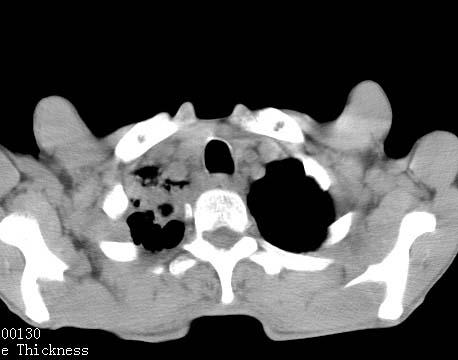

病人女 60岁 咳嗽 气促十余天,大叶性肺炎.

右肺上下叶均见 大片状密度增高影,边界清晰,其内可见支气管充气征,气管支气管通畅。纵膈略向右移位,其内无肿大淋巴结影。首先考虑炎性病变。不排除一些特异性的炎症。不知道发烧吗??wbc高吗??建议治疗后复查!!